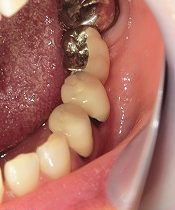

インプラントの被せ物

インプラントによる欠損の治療